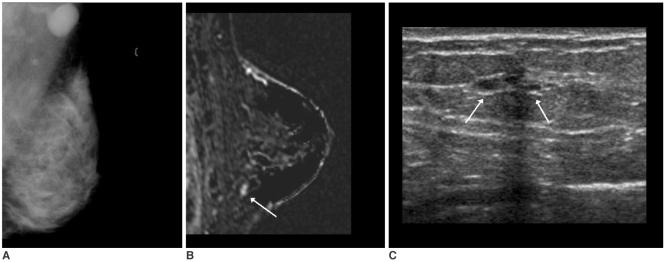

MR imaging detected occult breast carcinoma in 10 of 12 (83%) patients. Two MR-negative patients were free of carcinoma in the ipsilateral breast during their follow-up period (39 and 44 months, respectively). In nine out of 10 patients, the MR-correlated mammography and second-look sonography localized lesions that were not detected on the initial exam. All the non-MR-correlated sonographic abnormalities were benign.

Breast MR imaging can identify otherwise occult breast cancer in patients with metastatic axillary lymph nodes. Localization of the lesions through MR-correlated mammography and second-look sonography is practically feasible in most cases.